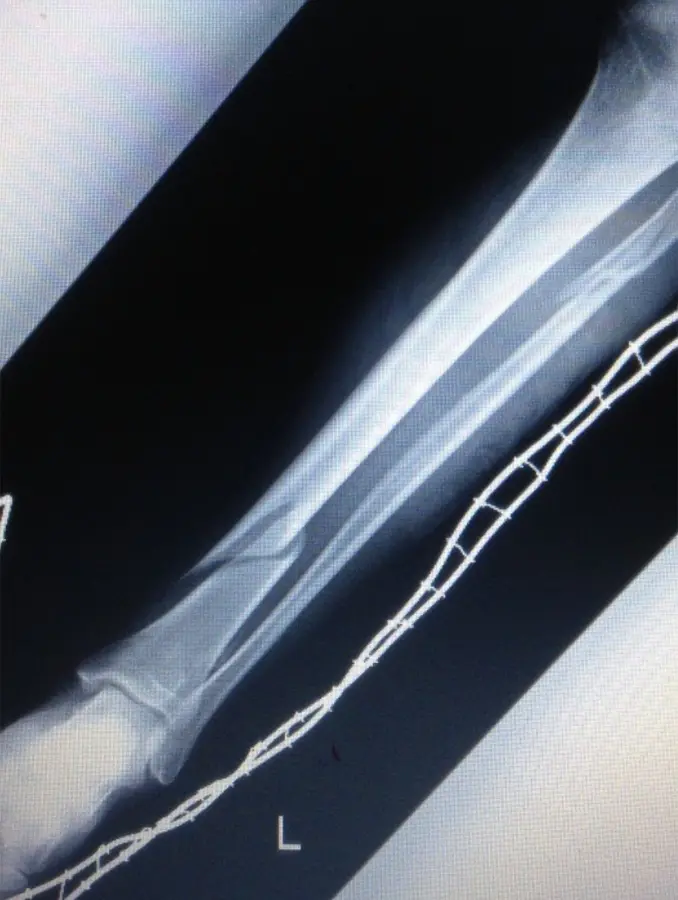

画像所見

初診時のX線にて脛骨遠位骨幹部、腓骨近位部、それぞれにらせん骨折(Müller AO分類 42-A1)を認めた。

(図1)単純レントゲン像